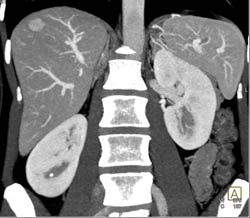

Diagnosis

Focal Nodular Hyperplasia (FNH)